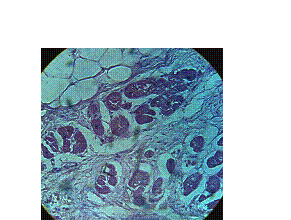

фиброз миокарда (Рис.1) и «веерообразные» гипертрофированные миокардиоциты с отеком сарколеммы, фиброз,

липоматоз стромы миокарда (Рис.2).

Рис.2. Б-ной Т., 25л. Стаж

каннабисной наркомании 8л. «Веерообразное»

расположение кардиомиоцитов, склероз, липоматоз стромы миокарда.

Окраска

гематоксилин и эозин; х 200